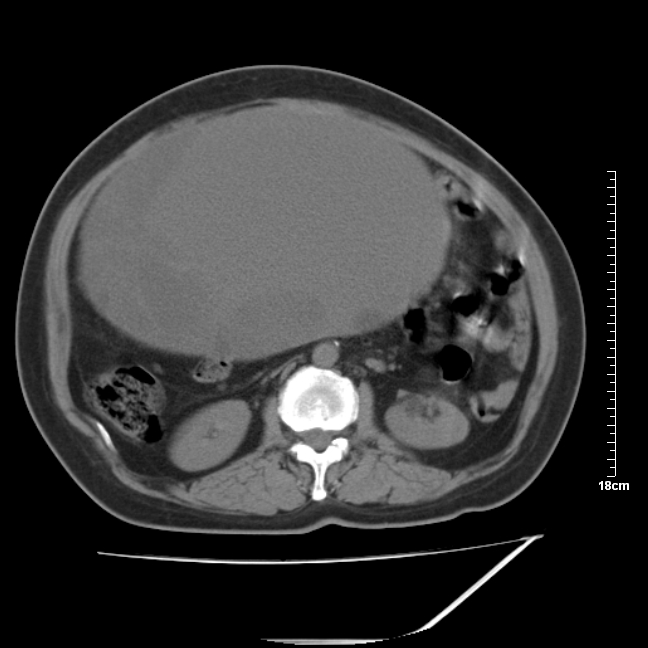

以下是引用jinning在2007-5-17 11:18:00的发言:[br]考虑右侧卵巢囊腺瘤合并少量出血可能性大